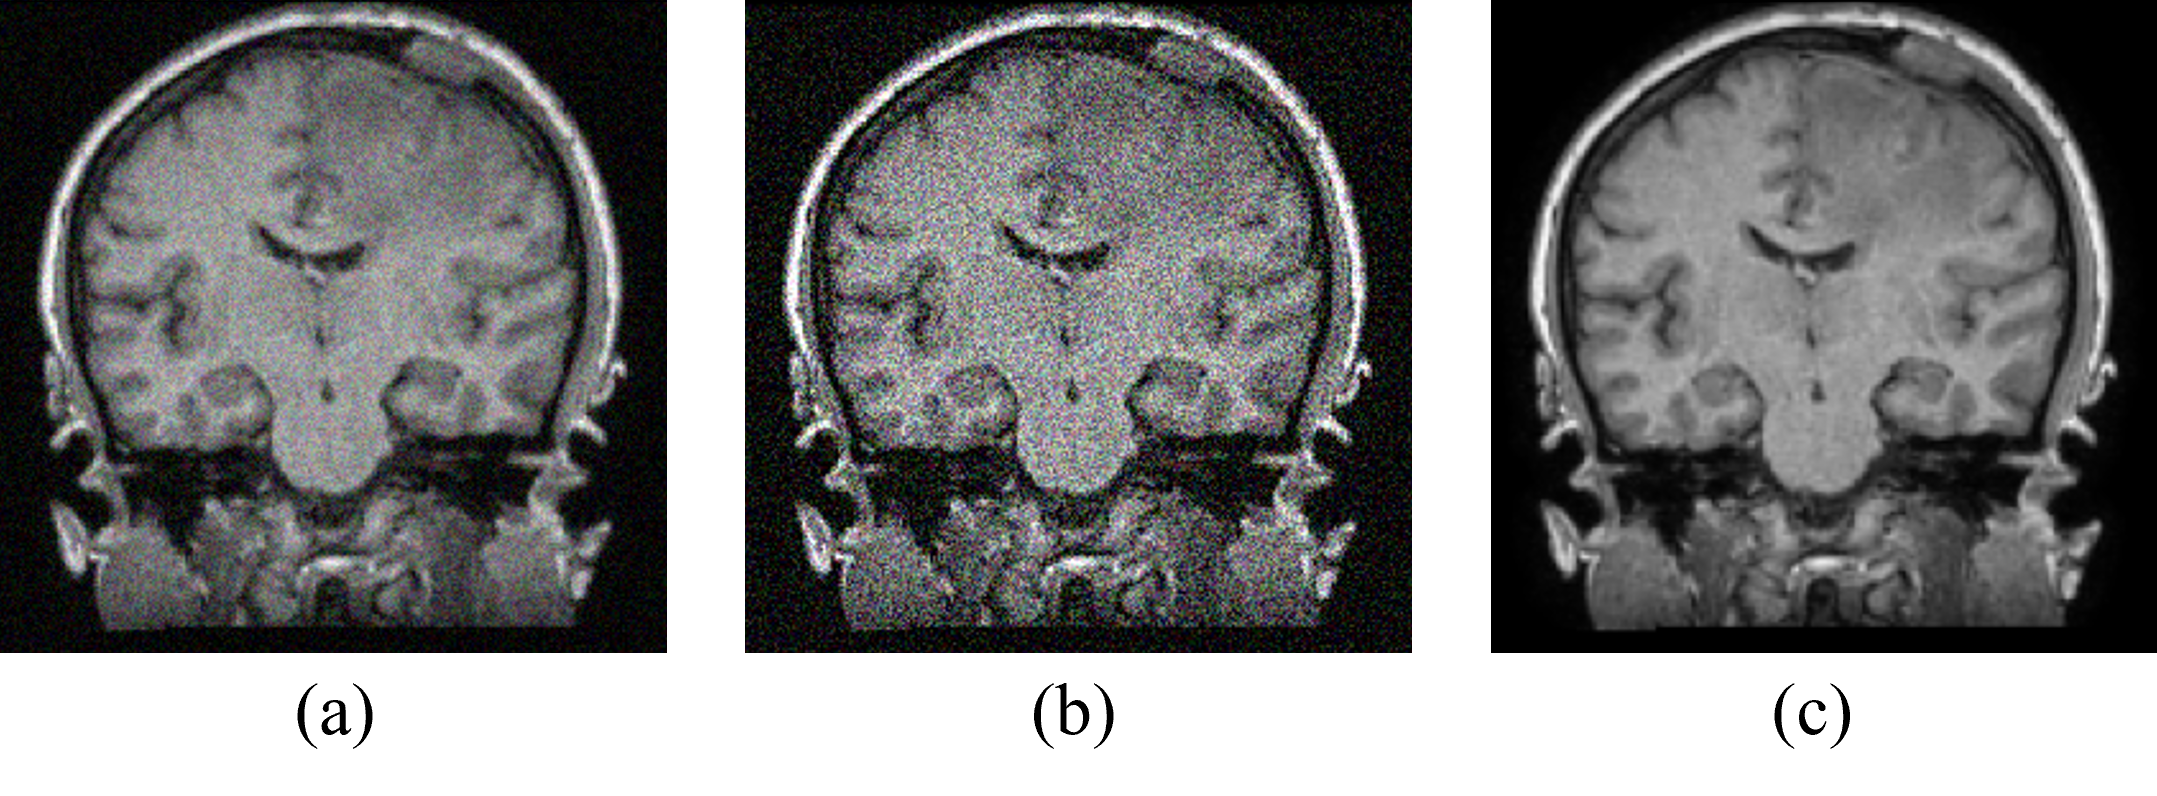

Figure 6: Ablation result for DiL: (a) given MRI, (b) reconstructed MRI without DiL, and (c) reconstructed MRI with DiL.

An additional CT to MRI abdomen image translation by all the conditioning scenarios is shown in Fig 5 (a) to (j). The real input abdomen CT image and corresponding target abdomen MRI image are shown in Fig. 5 (a) and Fig. 5 (f), respectively. Fig. 5 (b) presents the generated image from the proposed pCCGAN conditioned with images. One can observe that the edges are not clearly defined especially at the bottom part of the generated image. The output image generated by the conditioning of the average MRI image is displayed in Fig. 5 (c). Here, one can see that the image is a blur which leads to missing minute details. Fig. 5 (d) shows the result obtained by giving a PDF of an MRI image as the condition; one can make out from the image that the proposed CCGAN is not able to translate the input CT image to an MRI image. The output generated by the simple pCCGAN without augmentation is displayed in Fig. 5 (e). In this case, the image generated overshadows the low-frequency regions and the high-frequency region is enhanced. Fig. 5 (g) presents the image generated by the proposed pCCGAN when a patch of 8×8888\times 8 pixels is the condition provided. The network tries to translate the CT into MRI, however, the image remains patchy. The image generated by the conditioning of 16×16161616\times 16 pixels size patch is displayed in Fig. 5 (h). This conditioning helps the pCCGAN in optimal translation and restoration of the input CT image equivalent to the target MRI image as it utilizes the neighborhood pixel information also, both the high and low-frequency information is intact compared to the target modality. Fig. 5 (i) shows the result obtained by conditioning on patch size of 32×32323232\times 32 pixels. The low-frequency regions are not enhanced in this case, however, the image translation is comparable to the target image. The output obtained from conditioning on patch size of 64×64646464\times 64 is shown in Fig. 5 (j). In this case, the image contrast is increased and the high-frequency region is enhanced by a large amount. An ablation analysis with and without DiL is presented in Fig. 6 (a) to (c). The restored MRI with DiL shown in Fig. 6 (c) on the given MRI (Fig. 6 (a)) successfully reduces the noise content and artifacts present in the low and frequency portion of the images compared to the restored version without DiL (Fig. 6 (b)).